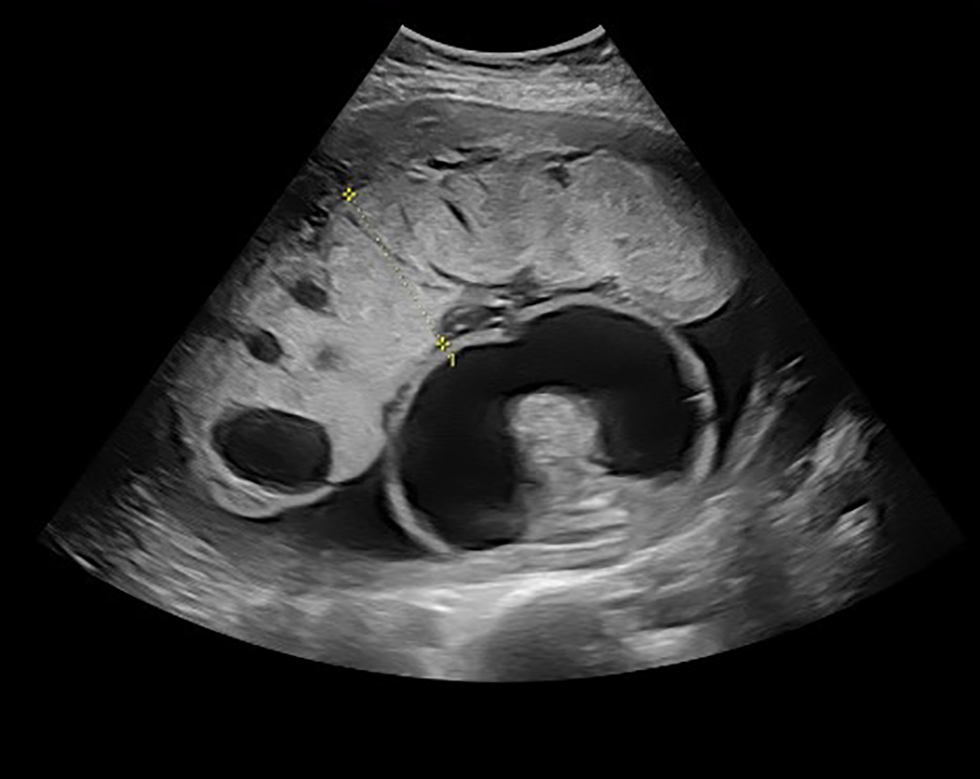

Ultrasound performed by Maternal Fetal Medicine demonstrated a single live intrauterine pregnancy at gestational age of 19+3 weeks. The fetus was affected by severe hydrops fetalis, as demonstrated by large pleural effusions, large ascites compressing the kidneys and body wall edema (Figure 1). The brain was very abnormal with bright cerebrospinal fluid and streaky echoes throughout the cortex (Figure 2). There was polyhydramnios with a maximum vertical pocket of 8 cm, with a thickened and overtly hydropic placenta (Figure 3). The umbilical artery Doppler ultrasound was abnormal with an increased systolic to diastolic ratio; however, the middle cerebral artery (MCA) Doppler did not demonstrate evidence of fetal anemia (peak systolic velocity 1.37 MoM). To complete the evaluation for hydrops, amniocentesis was performed and sent for microbiologic and genetic evaluation. Results are summarized in Table 2 and were notably positive for T. pallidum on PCR testing.

Figure 3: Enlarged, hydropic, placenta with multiple cystic lesions at 19+3 weeks gestational age

Text description: Figure 3

Ultrasound image, taken at gestational age of 19+3 weeks. An abnormal placenta is noted, with a thickened, hydropic appearance and multiple cystic lesions.